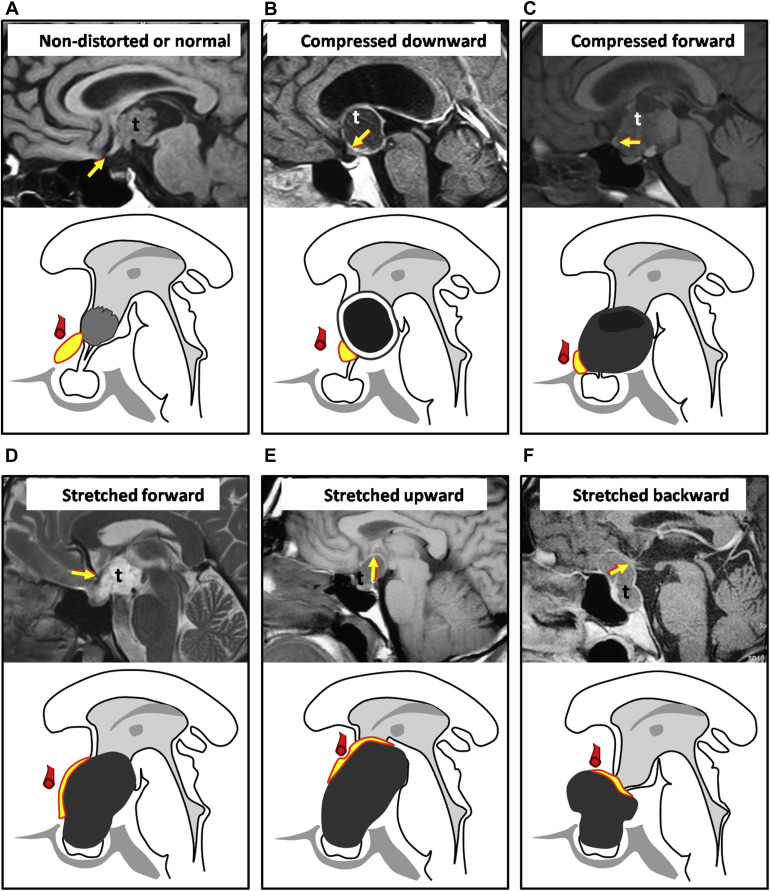

Dislokationen des Chiasma opticums

Schematische und MRT Abbildungen möglicher Dislokationen des Chiasma opticums. Abbildung adaptiert von Prieto et al. World Neurosurgery 2015.